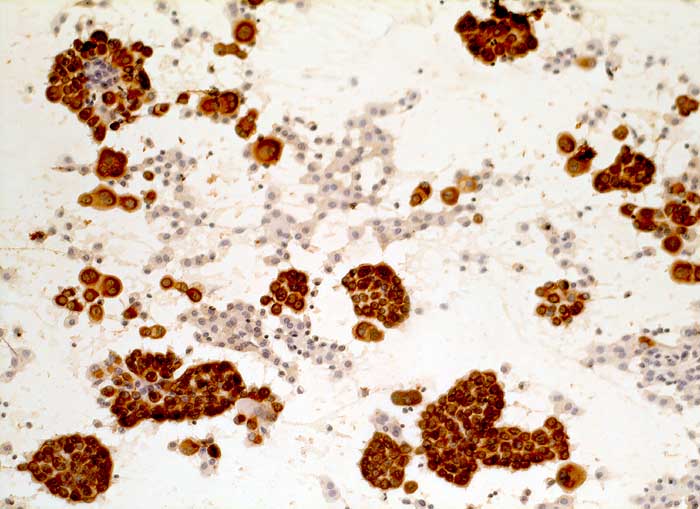

l/ Panzytokeratin (CK22/Lu-5)

Panzytokeratin (CK22/Lu-5)

Anfärbung:

Zytoplasma positiv.

Reaktion in Neoplasien:

Die meisten Karzinome und vereinzelte Sarkome reagieren positiv mit diesen Panzytokeratinen. CK22 ist etwas sensitiver und spezifischer als Lu-5. Entdifferenzierte oder sarkomatoide Karzinome können die Positivität für Zytokeratine verlieren.

Diagnostischer Nutzen:

Suchantikörper zur Abgrenzung von Karzinomen von Lymphomen, Sarkomen und malignen Melanomen. Identifikation von Karzinommikrometastasen in Lymphknoten.